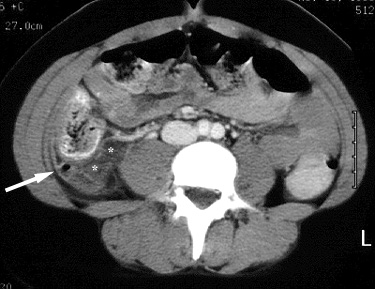

Figure 3. CT image at a lower level than Figure 2 shows a second appendicolith (large white arrow)within the fluid-filled dilated appendix. Note the similarity in appearance to the contrast-filled, dilated right distal ureter (small black arrow on the right; small black arrow on the left is the non-dilated distal left ureter). |

Figure 4. CT scan further caudal than Figure 3 shows the distal right ureter (black arrow) compressed by the adjacent dilated, fluid-filled appendix (A).B = urinary bladder. |

| Surgery revealed acute, non-perforated appendicitis. |